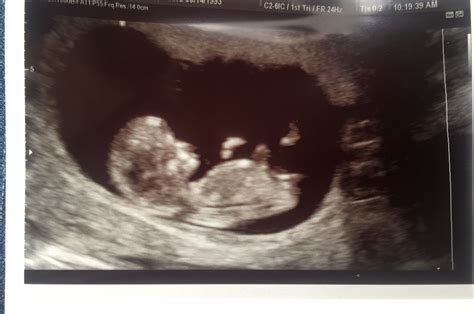

At 10 weeks, the fetus is about the size of a strawberry, measuring approximately 1.2 to 2.5 inches in length. The 10 week sonogram can reveal several key features:

• Heartbeat: One of the most exciting moments is hearing the fetus’s heartbeat, which is usually visible as a rapid fluttering on the screen.

• Crown-Rump Length (CRL): This measurement from the top of the head to the bottom of the buttocks helps to estimate the gestational age and ensure the fetus is growing at a normal rate.

• Basic Structures: The ultrasound can show the early development of the brain, spinal cord, and other vital organs. The limbs, tail, and yolk sac may also be visible.

• Amniotic Sac: The amniotic sac, which contains the amniotic fluid surrounding the fetus, can be seen clearly.

📝 Note: The clarity of the images can vary based on the position of the fetus and the amount of amniotic fluid present.